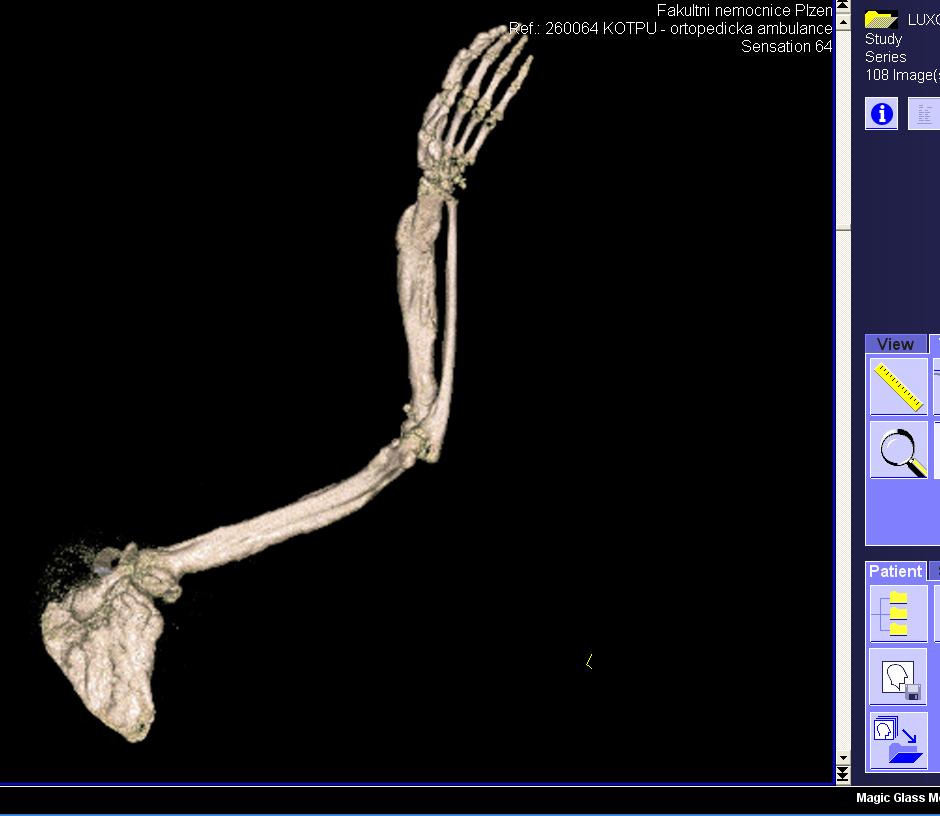

Area(s) affected:  Left arm and hand

I am sending you some photos from RTG and CT and scinti scam from last month.